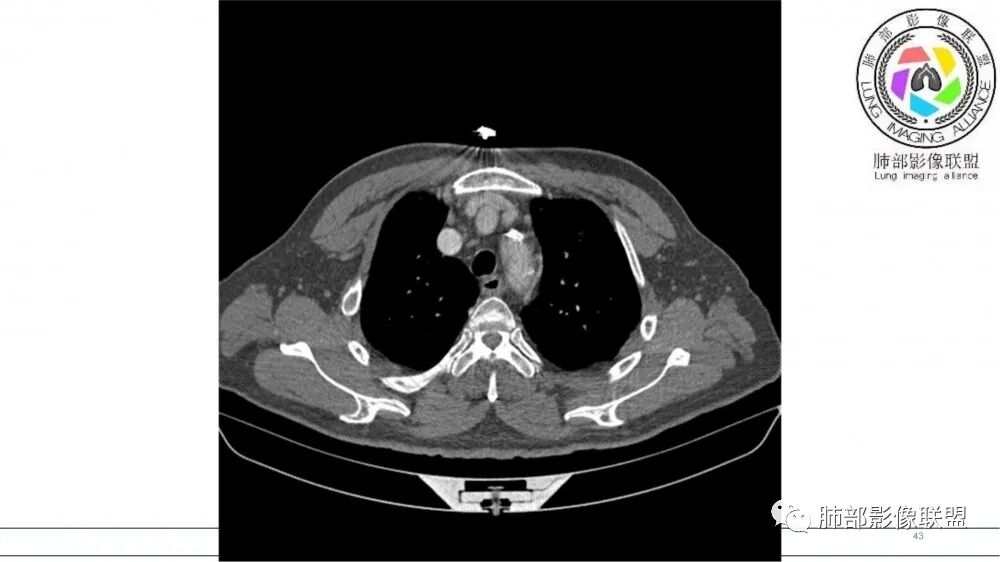

左肺上叶前段支气管内铸形生长软组织影,增强后均匀强化,远侧见斑片状磨玻璃影。考虑恶性病变,粘表?粘液腺?

老年男性,左肺上叶前段支气管内铸形阴影,增强后病灶不均匀强化,内部有坏死?远端可见斑片状阴影(阻塞性肺炎)。考虑恶性病变,老年人,鳞?类癌?粘表不能排除。

男,70岁,吸烟史,咳嗽,胸闷憋气一个月,左肺上叶不规则形软组织密度影,病灶沿支气管走形,周围见粟粒及棉絮样稍高密度影,增强扫描病灶内见少许坏死,考虑鳞癌可能,鉴别结核。

老年男性,肺气肿,吸烟史,左肺上支气管腔内铸型高密度影,呈指套状,远端多发树芽,增强不均匀强化,考虑鳞癌,鉴别小细胞癌

B3指套征,常规不是鳞癌就是ABPA,有强化丶血管造影征,倾向于鳞癌

老年男性,长期吸烟史。左上肺前段沿支气管走形的指套样病变,增强可见病灶强化(排除结核、ABPA(也无气喘症状)),远端多发点状高密度影。考虑恶性肿瘤,鳞癌可能性大。

指套征,扩张支气管内软组织强化,远侧肺野阻塞性炎,纵隔、左肺门肿大淋巴结;老年男性,吸烟,考虑鳞癌,鉴别小

指套征:是影像征象,胸部平片表现为手指状密度增高影,以肺门为中心呈放射状分布,CT显示扩张支气管内低密度黏液栓形成或实性病变,呈管状、树枝状或卵圆形密度增高影;支气管扩张伴近端梗阻时,扩张支气管内部黏液分泌物不能排出而形成。可以伴随远端空气潴留征、阻塞性炎症。